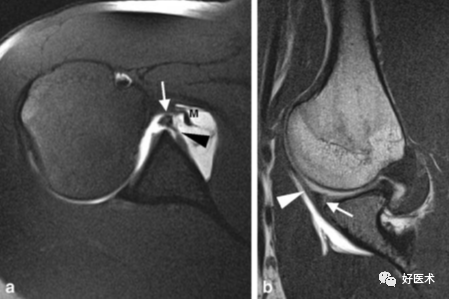

1.Bankart lesion

盂肱下韧带和前盂唇(前下盂唇韧带复合体)从关节盂边缘撕脱,伴肩胛骨骨膜的撕裂。首次损伤后不恰当愈合可导致反复肩关节不稳。

2.Bony Bankart lesion

前下盂唇韧带复合体从关节盂边缘撕脱,伴继发于前关节脱位的肩胛盂骨性骨折。

3.Perthes lesion

Bankart lesion的变异:前下盂唇韧带复合体从关节盂边缘脱离,但骨膜完整且向前内侧剥脱,因此盂唇可在正常解剖位置。